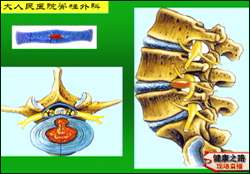

刘海鹰:腰椎神经根支配着下肢的感觉和运动,如图:神经根在受到压力的情况下就会产生相应所支配区域的疼痛。

王会民:退行性的腰椎疾病病情的发展是逐渐加重的,不同的腰椎疾病表现也是不一样的,比如单纯椎间盘突出的表现主要就是腰部和下肢的放射性疼痛,产生疼痛的原因是突出的物质对神经根产生了机械性的压迫同时突出物质还会释放一些化学物质对神经根产生化学性刺激。

刘海鹰:建议患者停止骶管疗法,骶管疗法只适合一些症状轻的患者,如图这位患者由于进行骶管注射治疗,手术时发现有严重的斑痕粘连。